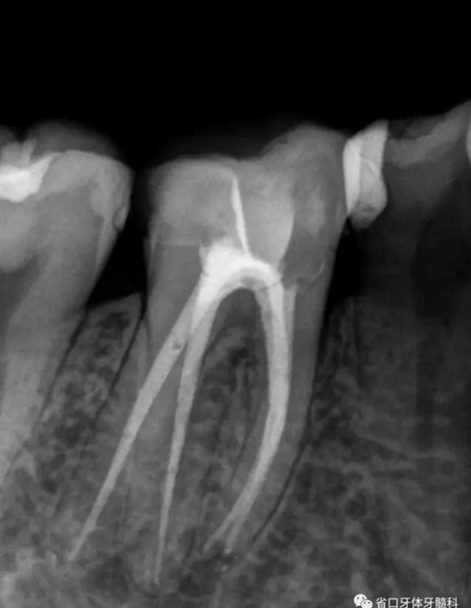

圖1 術(shù)前X線片:46/近中根面繼發(fā)齲,根尖周低密度影,遠(yuǎn)中舌側(cè)根管影像模糊;根分叉低密度影,近中牙槽骨見少許角形吸收。

處置:46/上橡皮障,顯微鏡下去齲、開髓、拔髓、探根管口4個。其中ML鈣化明顯,ET40蕩洗,導(dǎo)入EDTA輔助疏通細(xì)小彎曲ML,測長:22mm。鎳鈦預(yù)備根管,根尖寬度備至25#,超聲蕩洗,紙尖干燥,AH-plus+熱牙膠垂直加壓充填,GIC暫封。

圖2 術(shù)后根充片